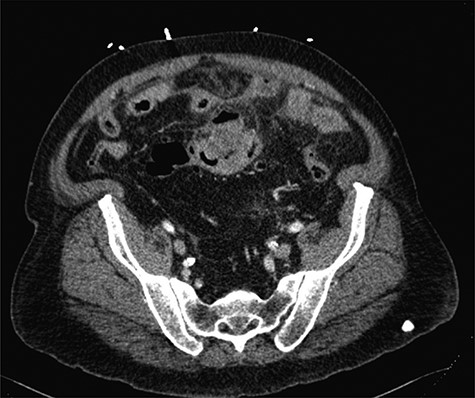

The patient is a 69-year-old white male with a history of diabetes mellitus, hypertension and 56 pack-year smoking who presented to our emergency department with abdominal distension and pain. Physical examination showed severe, diffuse abdominal tenderness with rebound and guarding consistent with peritonitis. Laboratory studies revealed a white blood cell count: 9.4 × 109 cells/L, hemoglobin: 10.9 g/dL, platelets: 370 × 109 cells/L and creatinine: 1.29 mg/dL. Computerized tomography (CT) imaging of abdomen/pelvis demonstrated thickening of the sigmoid colon, pneumoperitoneum, intraperitoneal free fluid, multifocal liver lesions, and peritoneal and omental implants concerning for metastatic perforated sigmoid carcinoma (Fig. 1). The patient was taken emergently to the operating room for an exploratory laparotomy. A perforated sigmoid and multiple liver and omental lesions were encountered. A sigmoidectomy with end colostomy, partial omentectomy and wedge resection of liver segment III were performed. The patient was admitted to the surgical intensive care unit where he received routine postoperative care.

Axial CT imaging of the abdomen, which demonstrates focal thickening of the sigmoid colon with surrounding free fluid.